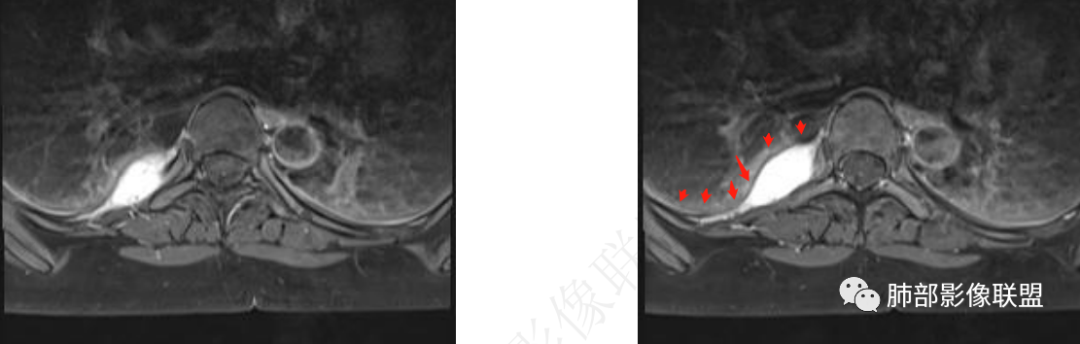

右后脊柱旁可见梭形软组织密度影,边缘清晰,与胸壁关系密切,增强后呈血管样同步强化,MRI呈长T1、长T2信号影,信号均匀,高亮T2有点灯泡征的感觉,考虑血管瘤,鉴别神经鞘瘤

海绵状血管瘤,明显强化,低信号间隔,点状低信号无强化血栓?机化?灯泡征;病灶软,又塑形爬行包绕

T2脂肪抑制序列高亮信号,T1等

血管样延迟强化

MRI表现:病灶多呈长T1长T2信号影,T2WI脂肪抑制序列呈高信号具有特征性,有时可显示流空血管影,弥散多不受限,增强后强化方式多样,与CT强化类似。

中青年女性,胸痛就诊,CT检查发现右后纵隔占位,病灶位于后胸壁纵隔移行区,略呈卵圆形或梭形蔓延,质地软,等/稍长T1、显著长T2信号,T2W脂肪抑制序列“亮灯”样高信号,这种磁共振信号特征对血管瘤具有强烈提示意义!(实在是太亮了,严格意义上的肿瘤罕见)

病灶显著强化,强化与纵隔大血管相仿且同期,一般会提示是血管源性病变,如血管瘤,如果边缘结节样强化逐渐填充渐进,则提示可能为海绵状血管瘤。